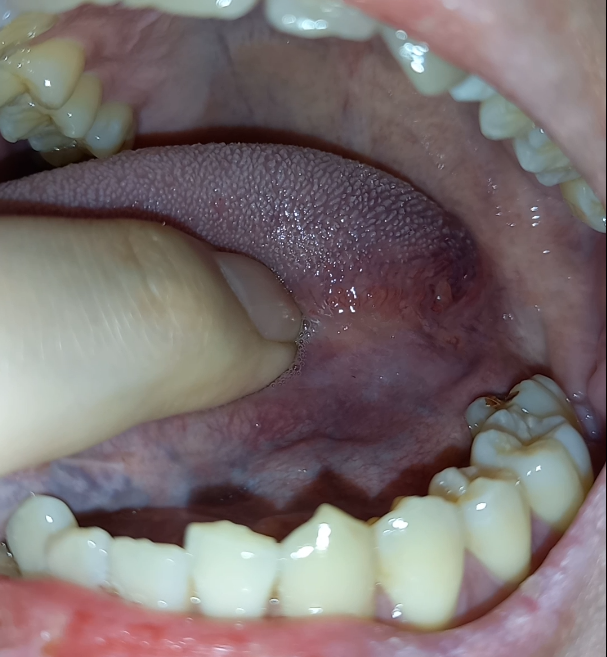

혀 측면 가장 안쪽 끝부분에 돌기같은게 있어요.

혀 측면 가장 안쪽으로 끝부분에 돌기같은게 나있는걸 발견하게 됐습니다.

혹시나 해서 반대편도 확인해보니 비슷한 돌기가 있더군요.

왼쪽 오른쪽 사진은 첨부해 두겠습니다.

돌기 위에 빨간 부위는 실핏줄같은거 같더라구요. 혀를 앞으로 당겨오니 보였습니다. 이것도 양쪽 다 보입니다.

양쪽에 보이는 돌기는 정상적인 구조물인건가요? 아님 치료가 필요한 건가요?

• 1번 째 사진

크기나 모양으로 봤을 때에는 점액낭종의 가능성은 있어보입니다. 지켜보시고 사라지지 않으면 치과 가보시면 됩니다.

사진으로 봤을 경우에는 큰 문제가 없어 보입니다. 구강 점막에는 가끔씩 점액종이라고 하는 것이 생기기도 합니다. 구강 점막이 과도한 자극에 의해서 마찰이 되면 내부의 조직액이 차에서 생기는 증상입니다. 크게 문제가 되진 않을 것으로 생각합니 됩니다. 자 자세한 확인을 위해서 치과에서 진료를 받아오세요.

사진에 보이는 돌기들은 정상적인 모습이고 첫번쨰 사진에 보이는건 물집이 잡힌거 같습니다. 큰 문제가 잇는건 아닙니다.